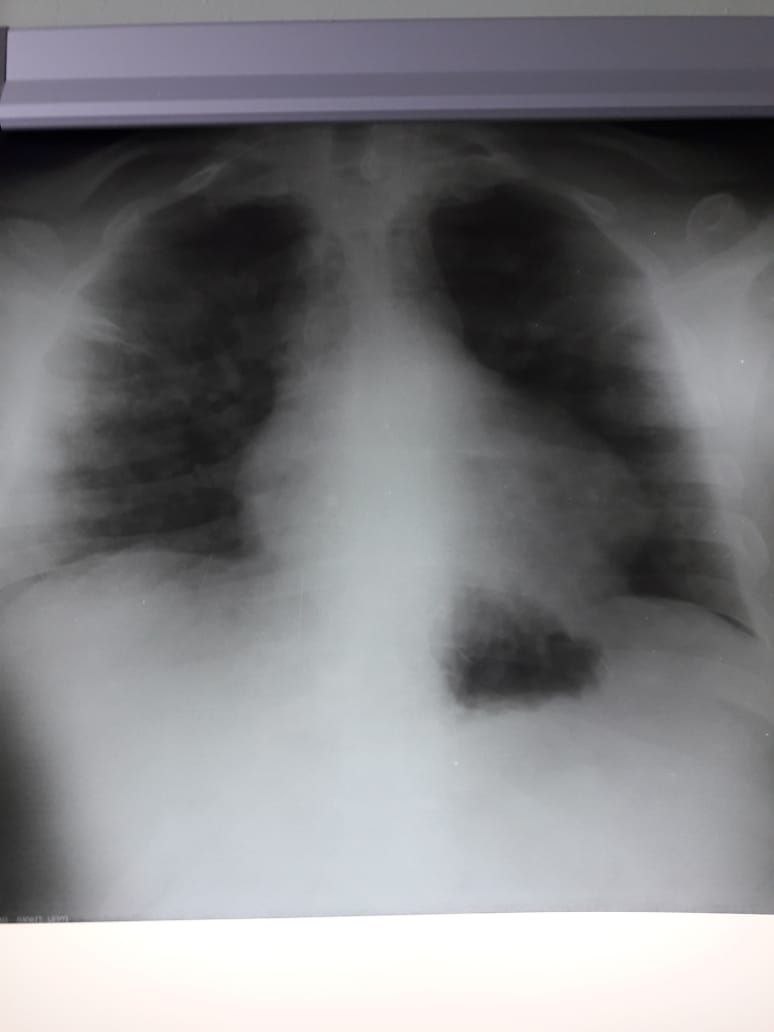

Javoxir Bahodir o'g'... in Radiology/Рентгенология Чатоид

Ж 85 лет

Жалует  на прогрессируюшии боли в правом гемитораксе

Плевральные наслоение

Да и средних зонах тоже

Вот вам снимок, обведите, где тут фиброз. Я его не вижу, поэтому и спрашиваю у вас

Обвести не могу функции не знаю на уровне 3 4ребер присмотрись